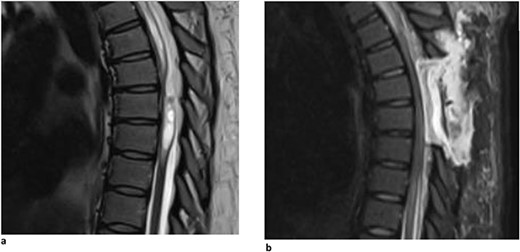

A 62-year-old woman presented with an extensive, multi-decade history of lower back pain that has progressively gotten worse over the last year. She initially presented in clinic with lumbar pain that radiated down her left anterior thigh, as well as significant thoracic pain that worsened with activities. She has a past surgical history of three lumbar laminectomies in 1983, 1988, and 1995 that caused temporary relief of her lumbar radiculopathy. In clinic, she stated that, during long periods of standing, she will experience buttock and lower extremity pain, as well as pain radiating to her anterior thigh and groin. She also said that she had increased difficulty with balance, causing her to use a rolling walker for ambulation. Physical examination demonstrated myelopathic symptoms with 3+ reflexes in both lower extremities and positive Babinski sign bilaterally. MR imaging of the spine was ordered and showed an arachnoid web displacing the spinal cord at the level of T3 (Fig. 3). Her current symptoms were treated nonoperatively with an epidural steroid injection that caused 80% relief of symptoms for 2–3 weeks. Three months later, she returned with increased bilateral shooting pain in the interscapular blade region. The patient will return in 6 months to proceed with a repeat thoracic MRI to evaluate for any interval changes.

Dorsal indentation demonstrated in thoracic spine preoperatively (Patient C).